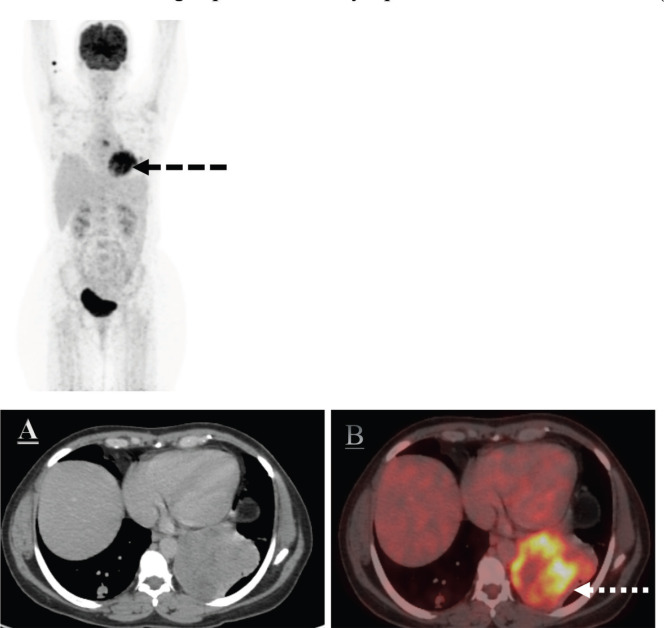

With the advent of next-generation sequencing, increasingly we can sub classify the soft tissue sarcomas into various subtypes with distinct prognostic and therapeutic implications. Sarcomas with RAF1 mutations are extremely rare and so far, the treatment strategies are not known. Here, we report a case of a 48-year-old lady who initially presented with right ear swelling, which was excised and was suggestive of dermatofibrosarcoma protuberans with S100 expression. After a disease-free interval of 25 months, the patient relapsed with metastasis in the lung. Repeat biopsy and next-generation sequencing (NGS) were suggestive of PDZRN3/RAF1 fusion mutated sarcoma. On presentation, the patient had an Eastern Cooperative Oncology Group performance status of 4 and had respiratory distress due to lung metastasis. After consensus and decision in the molecular tumour board, the patient was started on low-dose trametinib and doxorubicin. After three cycles of treatment, the patient had a partial response and post six cycles she had a near-complete response. This case exemplifies the value of molecular characterisation of soft tissue sarcoma and adds to the already sparse literature for RAF1 mutated sarcomas.

Abstract Image